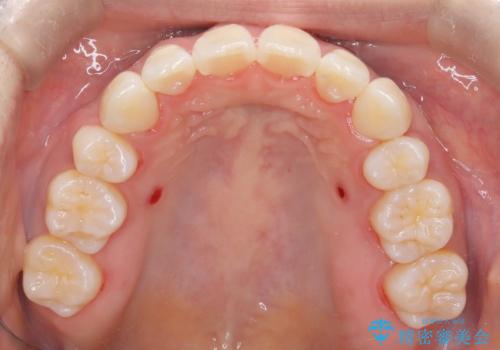

- 出っ歯、ガタツキ、噛み合わせが気になるとのことで来院された患者様です。

小臼歯を抜歯することでスペースを作り、前歯を下げて口元を下げ、Eラインを改善する治療方針としました。

表側のワイヤーは見た目が気になるとのことで、上の歯だけ裏側に付くハーフリンガルという装置で治療を行いました。

ワイヤー矯正治療では、抜歯を行うことで口元が引っ込み、理想的なEラインを形成することができます。抜歯によって、口元の輪郭が整って顔のバランスがより良くなります。これにより、お顔の印象が引き締まり、自然な笑顔が生まれます。